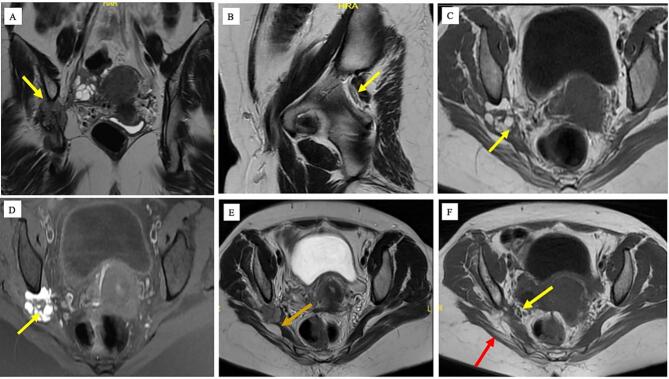

Thus, before the presentation reported here, the patient had consulted multiple specialists over a period of one and half years. At the current presentation, she was advised to have transvaginal ultrasound (TVS) and MRI of the pelvis. TVS was suggestive of DIE and MRI revealed a 4 cm endometriotic lesion involving the right sciatic nerve near the right greater sciatic foramen (Fig. 1). Extensive pre-operative multidisciplinary counselling was done, involving an endometriosis expert, orthopaedic surgeon and neurosurgeon, who were also later part of the operative team. A concomitant transgluteal and laparoscopic approach was planned.

Fig. 1.

: (A) The right sciatic nerve in sacrosciatic notch is completely effaced and encased by the mass. The length of the nerve involvement was ∼5.2 cm. (B) Left sacrosciatic foramen. The left sciatic nerve was unremarkable. (C,D) There was a definite mass noted on the right, posterolateral to the right ovary, clearly separate from it, external to the iliac vessels, suggesting extraperitoneal location in the sacrosciatic foramen. The mass was 32 × 16 × 30 mm with multiple coalescent small cysts abutting and anterior to the right sciatic nerve clearly posterior and separate from the right ovary and posterior to the right sacral plexus nerves. The cyst showed signal pattern of blood (T2 shading and T1 hyperintensity) with adjacent T2 hypointense thickening, suggesting chronic inflammation and fibrosis. (E) The sacral plexus nerves (sacral gluteal and pudendal are localised between the ovary and the sciatic neural endometrioma and no evidence of encasement was noted. (F) Muscles around the right hip joint show features of atrophy involving the right pyriformis muscle (Yellow arrow), right gluteal muscles (maximus, medius and minimus) (red arrow). (For interpretation of the references to colour in this figure legend, the reader is referred to the web version of this article.)